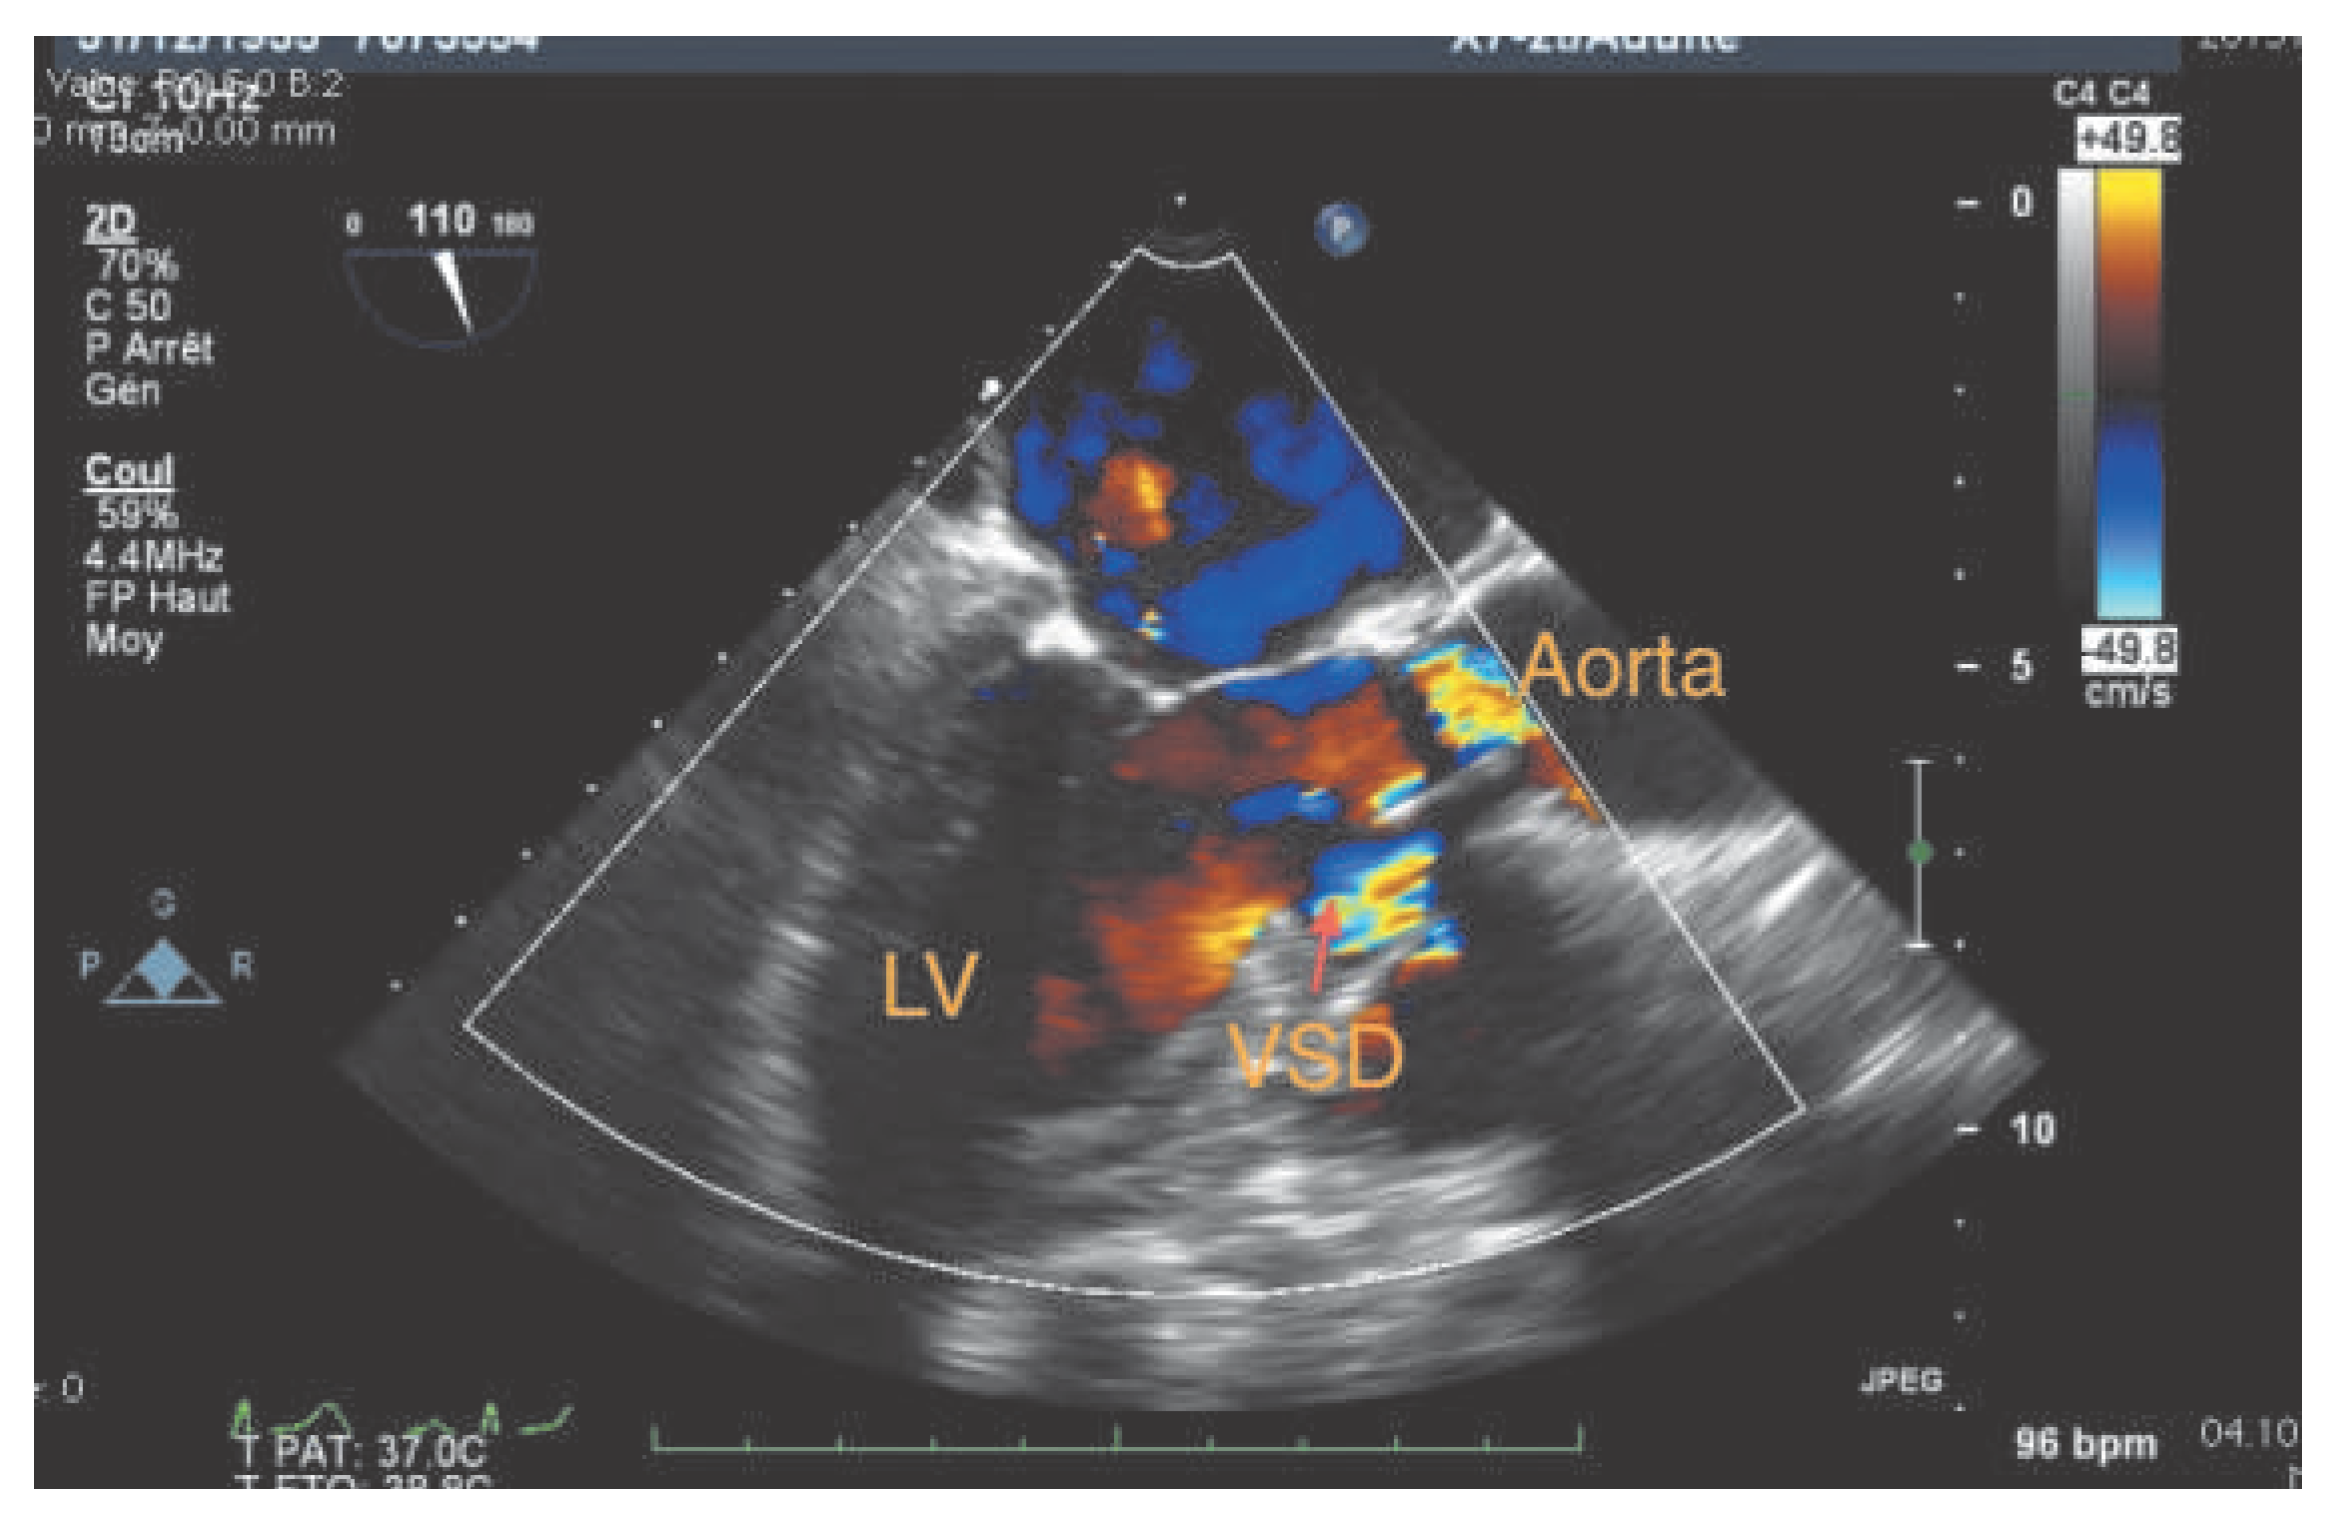

Case report